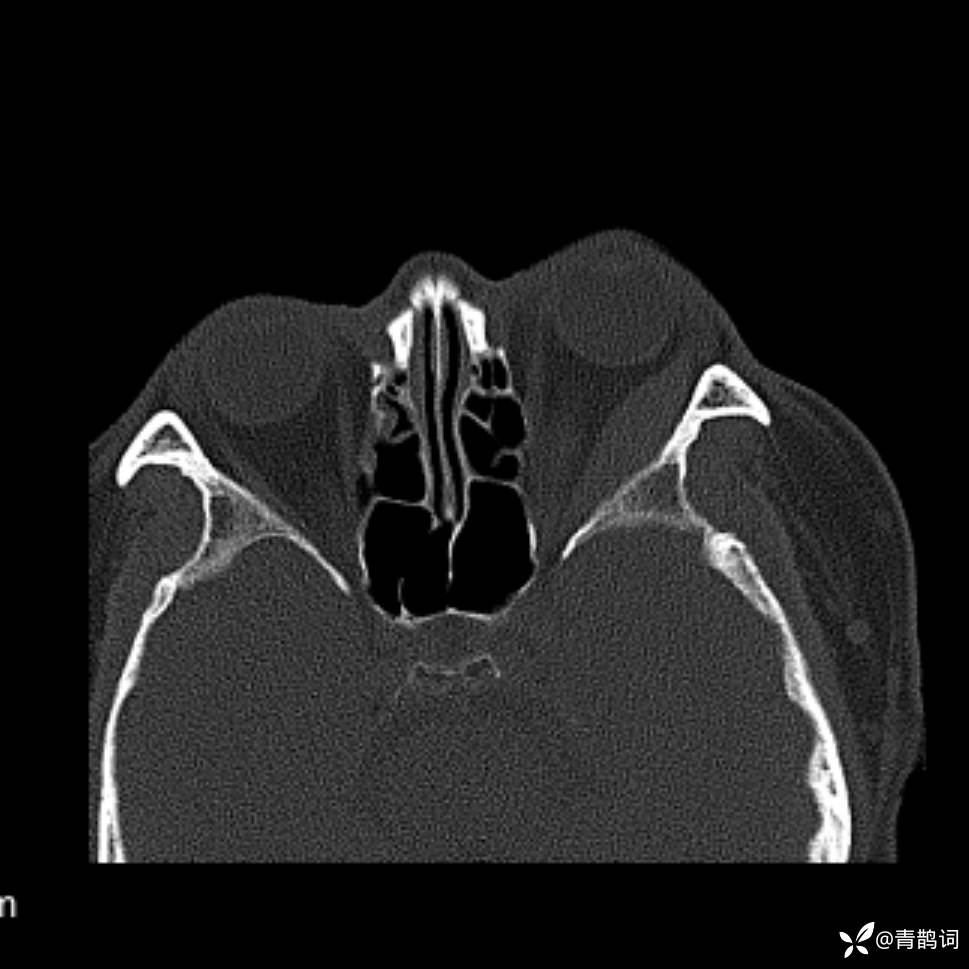

患者年龄:30岁。

患者性别:男。

简要病史:左颜面部肿胀2年,反复咳嗽咳痰,逐渐加重。

辅助检查

结合病史及影像学表现,期待评论区各位老师各抒己见~